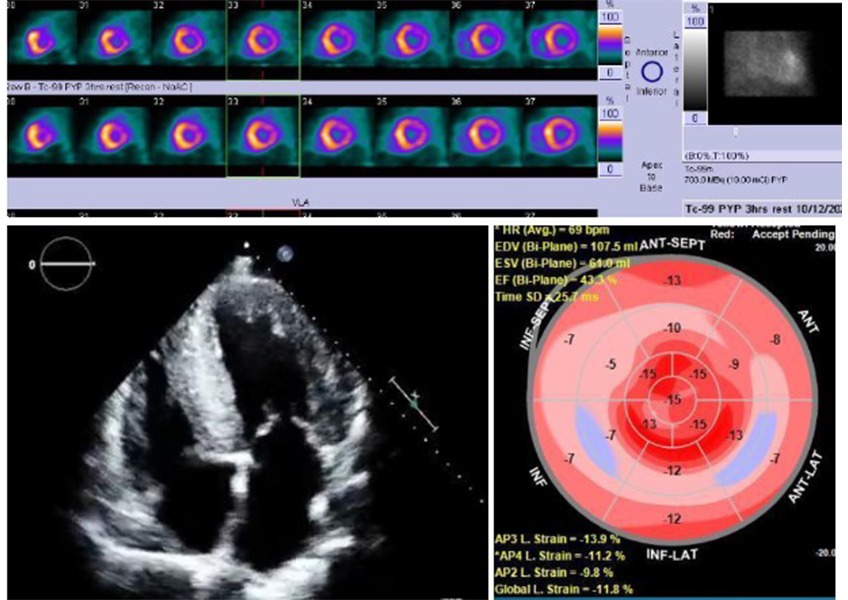

Dr. Almendal suspected amyloidosis, a buildup of abnormal proteins that can accumulate in the heart tissue and lead to heart failure, and ordered a CAT scan and genetic testing. The imaging found that the bottom part of his heart wasn’t pumping properly, and the workup confirmed it wasn’t hereditary — Tony had ATTR amyloidosis.